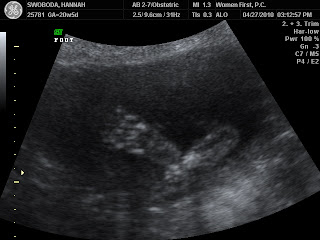

We had the ultrasound for our second baby today. Everything looks good, but they changed the due date to September 21, 2010. I am not convinced that the ultrasound tech's measurements are accurate, but I also am not opposed to accepting a later due date. I also think it's likely the original date was off by about a week. I think that the baby will probably arrive between the 9th and the 21. My official prediction is a due date of September 16, 2010.

Here are two profile shots.

A profile on the left, and face-on on the right.

A foot, and another face-on view.

Once again, the scary face-on view that looks like special effects from Harry Potter.